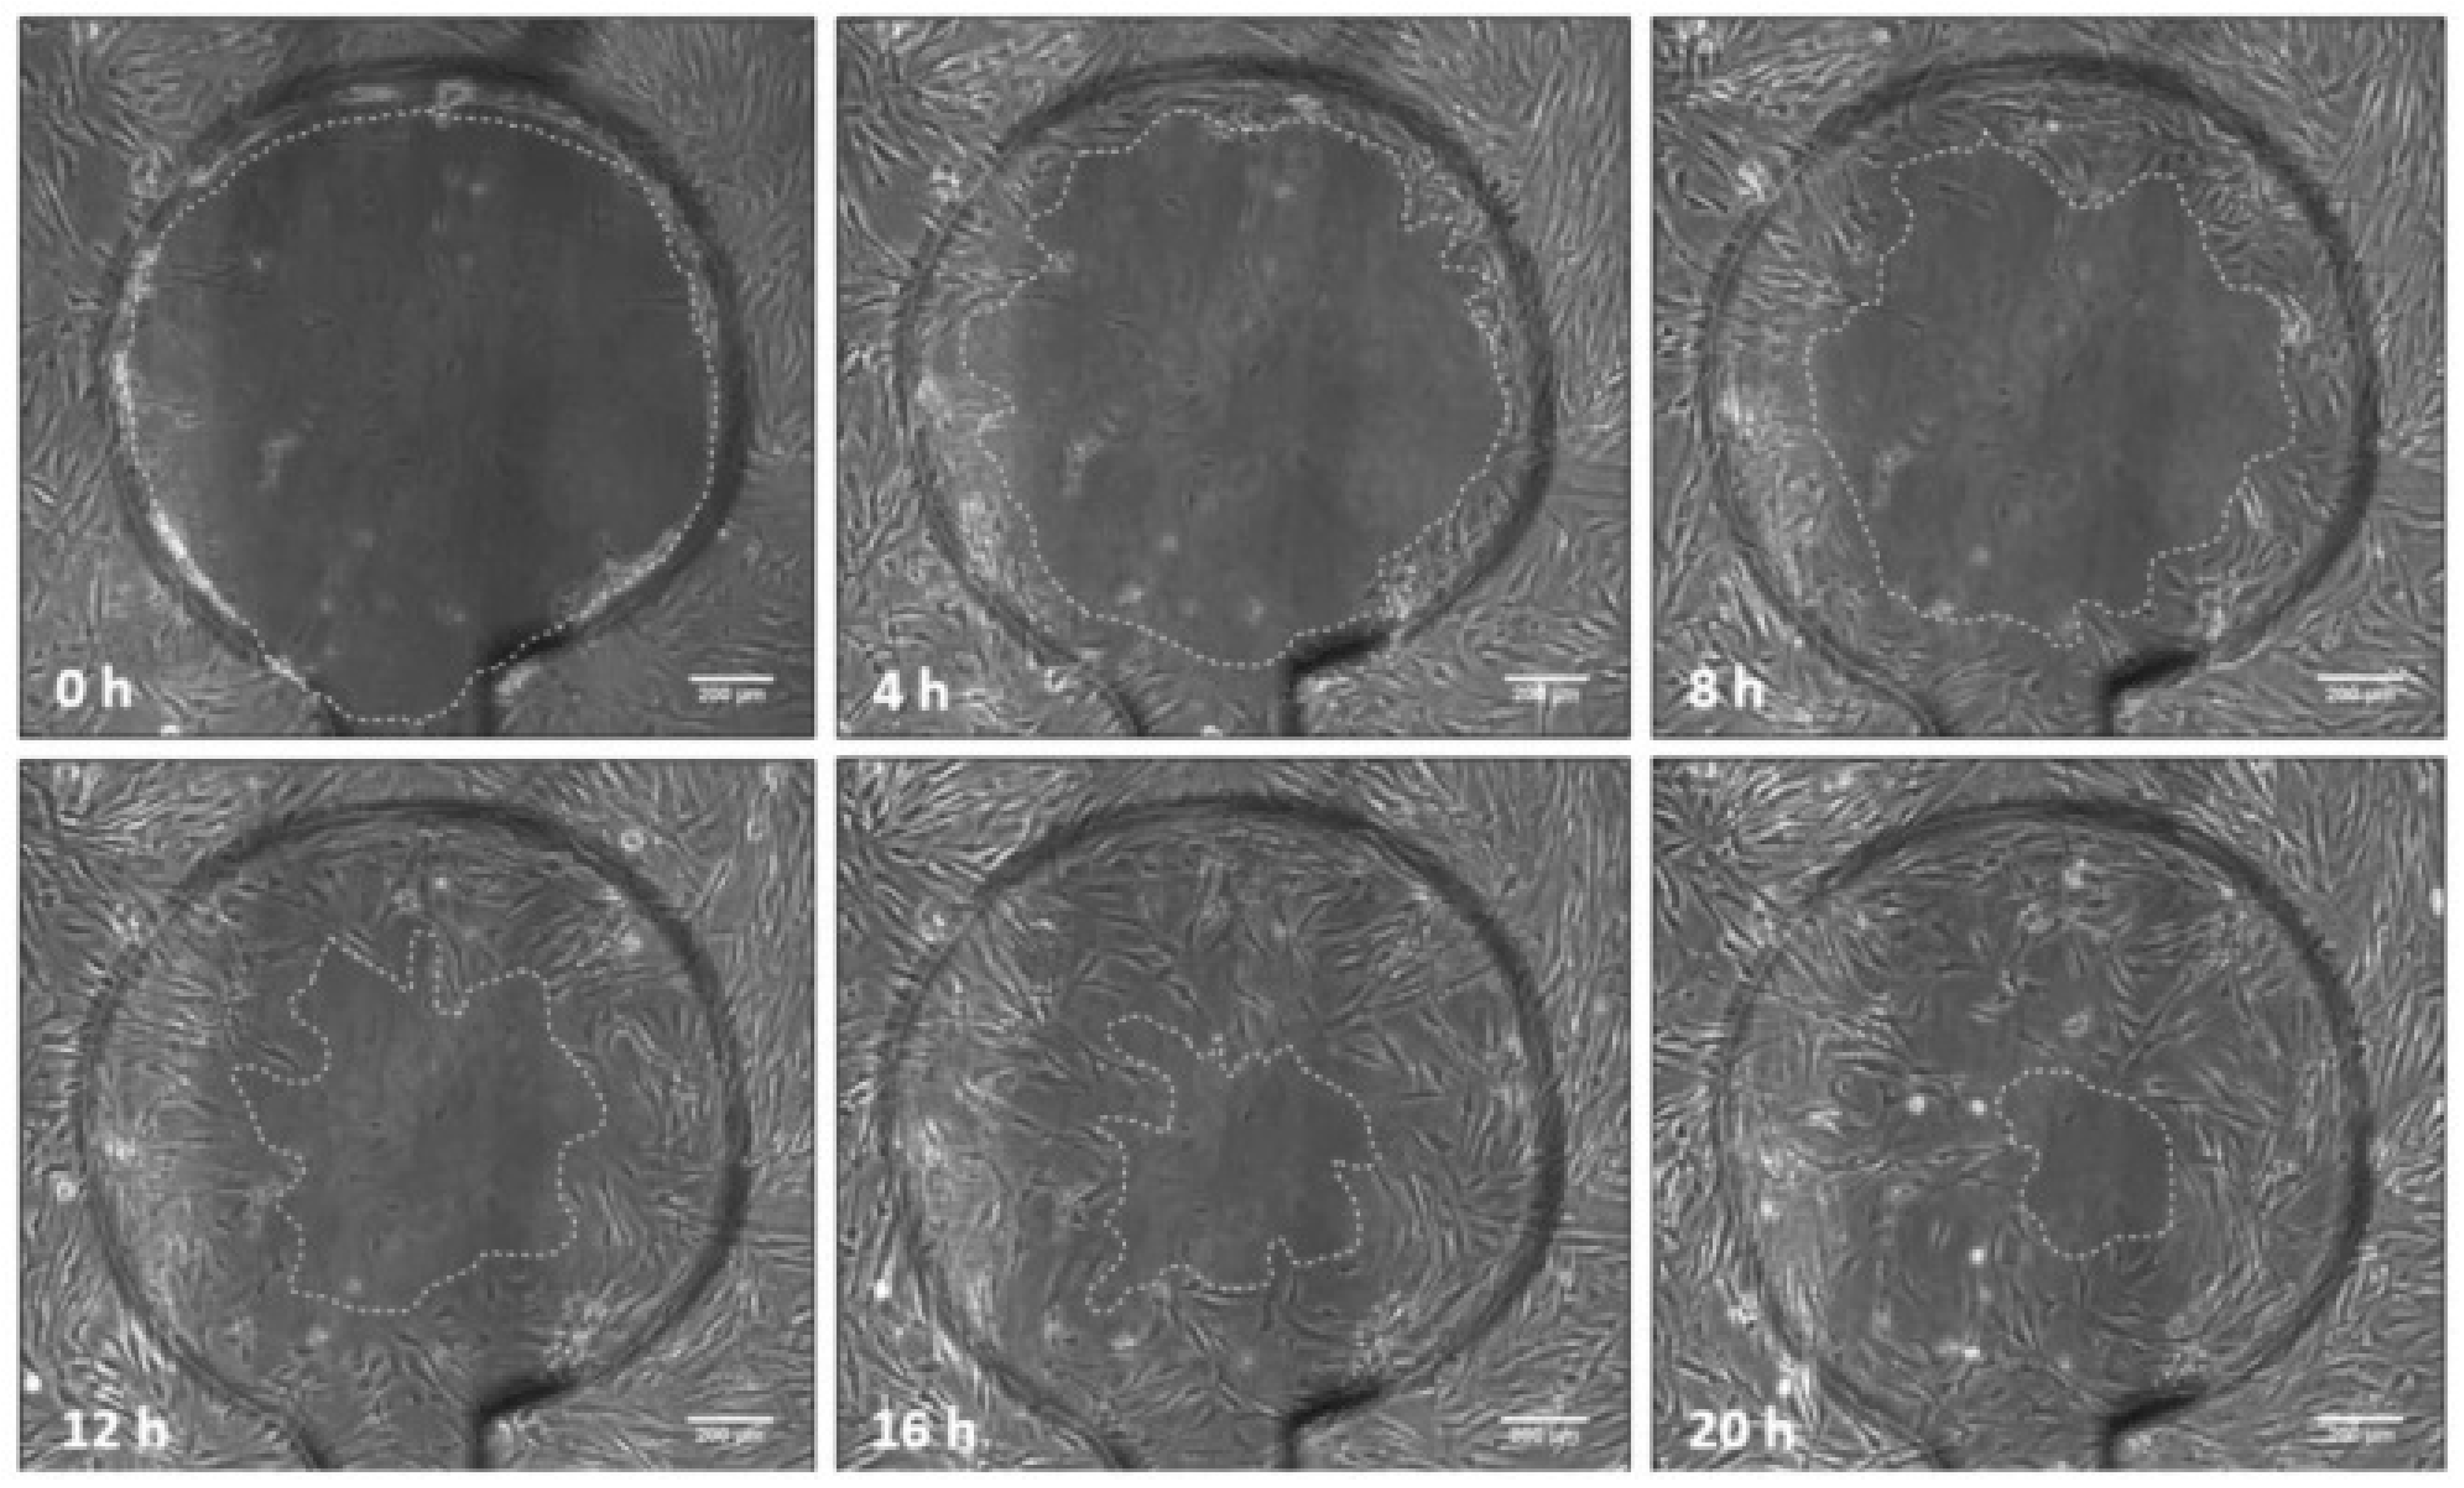

The basic principle of 2D wound healing assays involves the creation of cell-free region (wounds) in confluent cell monolayer deliberatively followed by monitoring of the wound healing process through analysis of collective cell migration and data acquisition (time-lapse microscopy, impedance measurement) as well as data evaluation [250].

Scratch Assay

The most common and well-established 2D in vitro wound healing assay is the scratch assay to assess the cellular and molecular mechanisms of cell migration for wound healing. In this simple and cost-effective method, wound or scratch is generally created mechanically to a cell monolayer followed by quantification of cell migration rate [246,251]. Scratch assay is one of the first developed 2D wound healing assays. In general, scratch is made in cell layer using cell scrapers, pipette tips, toothpicks, metallic micro-intenders, cell culture inserts, or ultraviolet rays [252,253,254]. Thereafter, the cell migration is quantified by measuring the width area, wound width, and relative wound density at defined time intervals using either area method, or wound closure rate method [255]. The advantages of scratch assay include in vivo cell migration mimicking ability, convenient capture of live cell migration, and monitoring of intracellular cellular events [256]. Despite its simplicity and cost-effectiveness, scratch assay suffers from several limitations including requirement of longer time (cell monolayer preparation and scratching), non-uniform cell monolayer, scratch width variation (irregular scratches), mechanical injury to cells and ECM, high resources requirement (cells, test compounds), accumulation of cells near edge of manually created gap, open and static cell culture system, and non-feasibility for high throughput screening [251,257,258]. Cell monolayer mechanical destruction is also possible by skin “stamping” methods. Furthermore, other methods to create wounds for healing assay include electrical, vacuum, PDMS barrier, thermal, laser and optical wounding. In recent years, newer scratching techniques for wound creation have been developed with research progress in this domain. The newer scratching techniques improve the reproducibility of in vitro wound assay as these are useful for creation of uniform scratches (shape and size). Furthermore, the creation of multiple scratches of uniform shape and size in one attempt is possible using these newer techniques. Some of the representative commercially available tools for scratching include AutoScratch™ wound making tool (BioTek), IncuCyte® WoundMaker (Sartorius), HTSScratcher (Peira Scientific Instruments), Cell Comb™ Scratch Assay (Merck), and Wounding Pin Tools (V&P Scientific, Inc.).